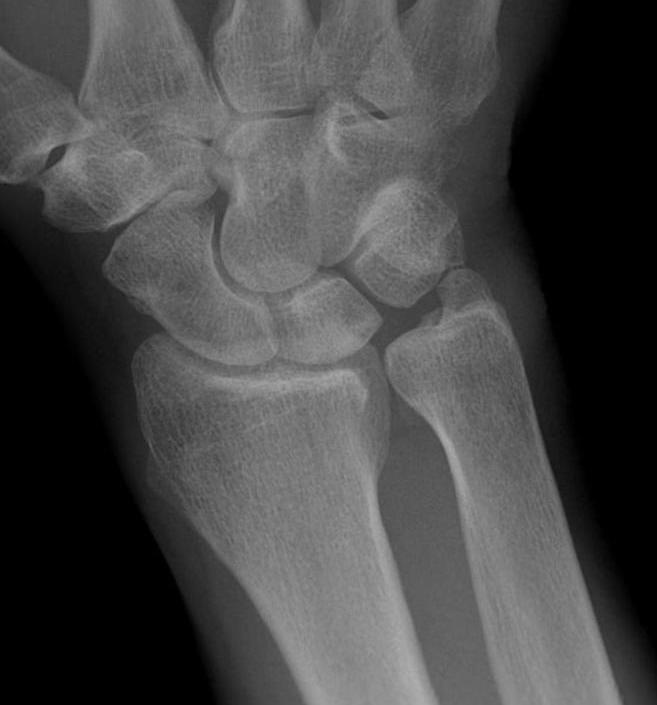

Ulna variance

Supination and pronation alter variance

- varies up to 3 mm with wrist position

- pronation increases ulnar variance

- supination decreases variance

90 / 90 view

- zero rotation view

- neutral supination / pronation

- PA film with wrist in neutral

- elbow 90° / shoulder abducted 90°

Line from lunate fossa and ulna head

- wide variation in population

- mean ulna variance is 1 mm (range 2 - 4)

Ulna neutral

Ulna positive

Ulna negative